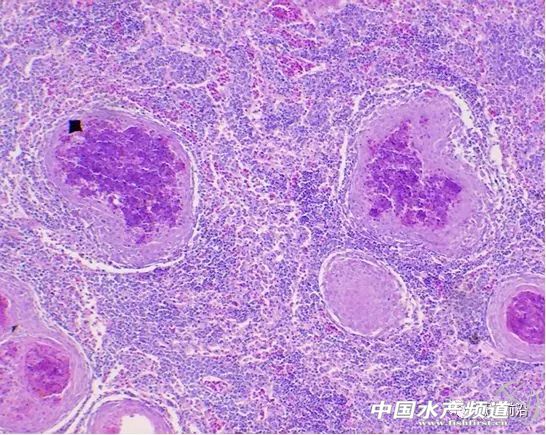

| 中國(guó)水產(chǎn)頻道原創(chuàng)報(bào)道, 加州鱸諾卡氏菌病防治技術(shù)探討 整理/ 鱖鱸前沿 李曉欣 本文整理自鱖鱸前沿第6期公開(kāi)課《加州鱸諾卡氏菌病防治技術(shù)探討》,課程嘉賓是廣州利洋水產(chǎn)科技股份有限公司廣佛區(qū)域經(jīng)理杜德群,長(zhǎng)按識(shí)別下方圖片二維碼可回顧本期課程。 加州鱸魚(yú)屬于鱸形目,鱸形目包括海鱸、生魚(yú)等是諾卡氏菌感染率較高的主要養(yǎng)殖品種。加州鱸是閉鰾類,鰾不完整,生活于中下層和底層,適合高密度養(yǎng)殖,耐低氧,不耐高氧,對(duì)氣體變化非常敏感,易得氣泡病(氧氣和氮?dú)猓?/div> 加州鱸爛身(潰瘍)病分為3大類:普通型爛身(氣單胞菌型)、膿瘡型爛身(諾卡氏菌型)及病毒型爛身(蛙虹彩病毒)。 普通型爛身 普通型爛身以氣單胞菌感染引起,病癥表現(xiàn)為爛身、爛鰭、爛嘴、爛眼、爛鰓等,發(fā)病初期可急性發(fā)生(以敗血癥為主),后轉(zhuǎn)為慢性(潰瘍),也可直接慢性發(fā)生。 魚(yú)體發(fā)生潰爛的前提是魚(yú)體有傷口,繼而感染到細(xì)菌引發(fā)潰爛。從實(shí)際的養(yǎng)殖生產(chǎn)來(lái)看,造成魚(yú)體受傷的原因主要如下: 1、氣泡病。實(shí)際中較多是由氣泡病造成的魚(yú)體受傷,這是鱸形目的魚(yú)受傷的重要誘發(fā)因素。 2、拉網(wǎng)。拉網(wǎng)過(guò)程中操作不當(dāng)會(huì)造成魚(yú)體受傷,從而繼發(fā)感染。 3、水變。水變之后魚(yú)體會(huì)出現(xiàn)鱗片脫落或爛尾等,緊接著就開(kāi)始爛身、爛嘴等等。 4、寄生蟲(chóng)。甲殼類寄生蟲(chóng)如錨頭蚤、魚(yú)虱等寄生,造成魚(yú)體受傷。 處理建議 普通型爛身的處理比較簡(jiǎn)單,急性的以氣泡病為主,急性死亡一般是氣泡病加重的,慢性的就按照細(xì)菌病處理。 細(xì)菌病處理可外用刺激性小的消毒劑,低劑量、間隔多次使用,以防反復(fù);內(nèi)服抗菌藥,這關(guān)鍵在于魚(yú)的吃料情況,如果魚(yú)吃料好,那么處理效果就好。 膿瘡型爛身 膿瘡型爛身是以諾卡氏菌感染引起,病癥表現(xiàn)為尾鰭、胸鰭基部,鰓蓋內(nèi)側(cè)等處潰爛、化膿,腎、脾、心臟等內(nèi)臟常有白點(diǎn),魚(yú)體缺乏維生素B時(shí)易發(fā)生,為慢性發(fā)生。如果池塘感染過(guò)諾卡氏菌,那么這個(gè)菌在池塘將會(huì)存活9年之久,最好要徹底清塘、清淤。 諾卡氏菌感染的病魚(yú)在體表有鰓結(jié)節(jié)型和軀干結(jié)節(jié)型兩類表現(xiàn)型: 1、軀干結(jié)節(jié)型 主要表現(xiàn)為軀干部的皮下脂肪組織和肌肉發(fā)生潰瘍,在外觀上則膨大突出成為許多大小不一、形狀不規(guī)則的結(jié)節(jié),剖開(kāi)結(jié)節(jié)后流出白色或稍帶紅色的濃汁,心臟、脾臟、腎臟、鰾等也有結(jié)節(jié),所有病灶處都有炎癥。 2、鰓結(jié)節(jié)型 主要表現(xiàn)為在鰓絲基部形成乳白色的大型結(jié)節(jié),鰓明顯褪色。多數(shù)發(fā)生在低溫期,廣東一般進(jìn)入到10月中下旬會(huì)出現(xiàn)這種情況。 在普通培養(yǎng)基上面分離諾卡氏菌,常溫條件下(25-28℃)需要10天以上,溫度稍高一點(diǎn)可能要7天,即諾卡氏菌最少需要一周才能從培養(yǎng)基上生長(zhǎng)出來(lái)。 諾卡氏菌 所以說(shuō)諾卡氏菌病是慢性病,這意味著如果魚(yú)塘出現(xiàn)大批量死亡,檢測(cè)發(fā)現(xiàn)很多魚(yú)已經(jīng)感染諾卡氏菌,這時(shí)一定不是諾卡氏菌造成的死亡,而可能是魚(yú)體感染諾卡氏菌后體質(zhì)弱,氣候環(huán)境變化、“三殺一消”、缺氧、氣泡病、繼發(fā)或并發(fā)氣單胞菌、寄生蟲(chóng)感染、病毒發(fā)作等導(dǎo)致死亡量猛增,大家在處理這個(gè)病害時(shí)不要糾結(jié)于諾卡氏菌,這是很重要的一個(gè)關(guān)鍵點(diǎn)。 肝臟 頭腎 后腎 脾臟 有養(yǎng)殖戶會(huì)疑問(wèn),諾卡氏菌是從哪里來(lái)的?實(shí)際上應(yīng)該是從冰鮮魚(yú)帶入,最早諾卡氏菌是從海水魚(yú)發(fā)現(xiàn)的。近幾年的走訪來(lái)看,四川、貴州一帶諾卡氏菌的發(fā)病率很低,當(dāng)?shù)乇r養(yǎng)殖比例很小,江浙一帶發(fā)病率高,廣東發(fā)病率也是比較高,尤其在2007-2010年期間發(fā)病非常厲害。 2008年左右佛山很多養(yǎng)殖戶還不認(rèn)識(shí)這個(gè)病,當(dāng)時(shí)把白點(diǎn)叫做孢子蟲(chóng),直到2012-2013年觀念才慢慢開(kāi)始轉(zhuǎn)變,但目前也有很多人還認(rèn)為它是孢子蟲(chóng)。在這里需要糾正一點(diǎn),目前加州鱸魚(yú)暫時(shí)還沒(méi)有發(fā)現(xiàn)孢子蟲(chóng)感染的情況,實(shí)際上孢子蟲(chóng)對(duì)于鱸形目的魚(yú)不是太敏感,所以大家在這方面不要有誤區(qū)。 治療方法 諾卡氏菌病的治療難度較大,目前還沒(méi)有能把諾卡氏菌完全抑制住的藥物,而殺菌力強(qiáng)的藥物毒性、副作用也非常大,建議大家選擇藥物時(shí)要慎重。諾卡氏菌是革蘭氏陽(yáng)性菌,治療上可內(nèi)服抗革蘭氏陽(yáng)性菌的藥物,如氟苯尼考、阿莫西林、硫酸新霉素等有一定抑菌效果,但無(wú)法徹底根治,同時(shí)注意耐藥性。 預(yù)防措施 1、防受傷:氣泡病是引起鱸魚(yú)受傷的重要原因,另外拉網(wǎng)、分池、分塘等也容易引起魚(yú)受傷,要注意預(yù)防。 2、補(bǔ)充維生素:養(yǎng)殖過(guò)程當(dāng)中要勤補(bǔ)充維生素,特別是從冰鮮魚(yú)轉(zhuǎn)向膨化飼料以后,膨化料里的維生素特別是維生素B族要多補(bǔ)充。 3、防繼發(fā)感染:可每隔7到10天左右拋網(wǎng)檢測(cè)魚(yú)體有沒(méi)有寄生蟲(chóng)、細(xì)菌等感染。 諾卡氏菌感染是慢性病,死亡率不會(huì)太大,幾條或十條,當(dāng)池塘魚(yú)出現(xiàn)小規(guī)模死亡時(shí)是本身病的問(wèn)題;但如果池塘魚(yú)出現(xiàn)大規(guī)模的死亡,幾十、上百甚至過(guò)千條,就不是本身病的問(wèn)題,而可能是魚(yú)體感染諾卡氏菌后體質(zhì)弱,氣候環(huán)境變化、“三殺一消”、缺氧、氣泡病、繼發(fā)或并發(fā)氣單胞菌、寄生蟲(chóng)感染、病毒發(fā)作等導(dǎo)致死亡量猛增,所以一定要分析清楚病程,而不要在諾卡氏菌本身這個(gè)問(wèn)題上太過(guò)糾結(jié)。 實(shí)際上,加州鱸諾卡氏菌病還是防重于治,因?yàn)楹芏嘣谥委煏r(shí),魚(yú)發(fā)病后已經(jīng)不吃食了。由于地區(qū)、養(yǎng)殖模式等不同,加州鱸魚(yú)的諾卡氏菌發(fā)病的程度也不一樣,建議大家根據(jù)當(dāng)?shù)仞B(yǎng)殖模式、放養(yǎng)密度等針對(duì)性處理。 互動(dòng)交流實(shí)錄 01、諾卡氏菌主要是什么原因?qū)е碌哪兀?/b> 杜德群:諾卡氏菌本身就是一個(gè)細(xì)菌,最早是發(fā)生從海水魚(yú)上分離到的,所以冰鮮魚(yú)是一個(gè)非常重要的傳染源。需要強(qiáng)調(diào)的一點(diǎn)是,諾卡氏菌的核心問(wèn)題還是魚(yú)體受傷,如果魚(yú)體不受傷,諾卡氏菌是沒(méi)有機(jī)會(huì)感染魚(yú)的。另外,實(shí)際上很多病都是病從口入的,建議大家勤預(yù)防,多補(bǔ)充一些維生素,增強(qiáng)魚(yú)的體質(zhì),包括抗病力、抗低氧、抗應(yīng)激能力。 02、諾卡氏菌病具體怎么處理? 杜德群:對(duì)于細(xì)菌病,一方面是外用消毒劑,另一方面是內(nèi)服抗菌藥。諾卡氏菌病是一個(gè)慢性病,魚(yú)感染后吃料會(huì)減慢,有的甚至不吃料。所以在內(nèi)服上如果池塘的魚(yú)吃料正常,治愈幾率還是非常大的,但如果魚(yú)吃料狀況非常差,甚至都不吃料了,只能外用藥,外用實(shí)際上不是在處理諾卡氏菌,而是預(yù)防其他的細(xì)菌感染。 處理過(guò)程當(dāng)中還要注意看死亡率, 如果魚(yú)死亡率比較高,幾十條或者甚至上百條死亡時(shí),一定不是諾卡氏菌的問(wèn)題,而可能是以下原因引起:水質(zhì)惡化、缺氧、消毒殺菌用藥劑量較大、刺激性很大等,從而加重了死亡。 03、外用什么藥比較好? 杜德群:一般的消毒劑都是有效的,推薦使用刺激性較小的,比如像一些聚維酮碘、苯扎溴銨,還有苯扎溴銨和戊二醛的一些合劑。其實(shí)外用消毒中,消毒兩個(gè)字是要加雙引號(hào)的,消毒是直接把這個(gè)病原體包括孢子殺滅的,但水體消毒其實(shí)是指抑菌,把菌的數(shù)量和毒性降低,起到控制菌數(shù)量的過(guò)程。 需要提醒大家的是,用藥時(shí)一定是從低劑量到高劑量,假如藥的使用說(shuō)明書(shū)是一瓶用兩畝,第一次使用時(shí)可以一瓶用四畝,然后看第二天的死亡量,如果第二天的死亡量沒(méi)有變化甚至在減少,那就同樣的分量繼續(xù)使用;如果死亡量還在增加,說(shuō)明藥物的用量對(duì)魚(yú)還是有刺激的,需要迅速解毒、改善環(huán)境、加強(qiáng)增氧,這時(shí)就不能消毒了,可能池塘水質(zhì)比較差,或是魚(yú)發(fā)病比較嚴(yán)重,體質(zhì)較弱。所以在大家在外用藥的時(shí)候,切記一定是從低劑量到高劑量,低劑量多次使用。 04、感染過(guò)諾卡氏菌的池塘干塘之后該如何消毒? 杜德群:最好的辦法就是清淤,之后曝曬。有些清淤之后馬上回水,這種做法不太合理,建議要有一段太陽(yáng)曝曬的過(guò)程,通過(guò)照射消毒讓塘底修復(fù)。另外,清塘以后可以使用一些穿透力比較強(qiáng)的氯制劑等,效果還是不錯(cuò)的。 05、內(nèi)服藥具體要怎么搭配??jī)?nèi)服的療程和劑量怎么把握? 杜德群:內(nèi)服藥建議大家最多不要超過(guò)三種,可以分成三類,也可以分兩類,或者加重一個(gè)品類的劑量,比如選擇阿莫西林時(shí),你就要選擇多補(bǔ)充一些維生素,因?yàn)榘⒛髁謿埩簟⒋x時(shí)間比較久,另外可以補(bǔ)充一些保肝的。 有些養(yǎng)戶朋友會(huì)加入一些磺胺類的藥,磺胺類的藥對(duì)于諾卡氏菌本身的抑菌效果是非常好的,但有較大的副作用,對(duì)肝臟和腎臟的損傷非常大,建議使用磺胺類藥物時(shí)劑量要逐步降低,從高劑量到低劑量慢慢減少;阿莫西林就低劑量、多次使用;氟苯尼考分量可以用重一點(diǎn),但它對(duì)諾卡氏菌實(shí)際效果并不是太理想;硫酸新霉素有些養(yǎng)戶朋友用的分量很重,但魚(yú)的腸道對(duì)它的吸收能力不是很強(qiáng),很快就排除了,雖然濃度大了抑菌效果好,有的時(shí)候可以加一點(diǎn),但還是不太建議。 內(nèi)服的療程要看池塘的死亡量和吃料狀況,一般情況下,第一個(gè)療程大概在5-7天,間隔3天左右,再內(nèi)服3到5天;然后間隔5-7天,再內(nèi)服2-3天;然后間隔10-15天,再內(nèi)服1-2天。后期就多補(bǔ)充維生素,特別是B族類的維生素。 06、如何正確診斷加州鱸諾卡氏菌病呢? 杜德群:如果養(yǎng)殖經(jīng)驗(yàn)比較久,實(shí)際上肉眼都能分辨,如果魚(yú)感染諾卡氏菌,皮膚表面有膿包,用手一擠,會(huì)出現(xiàn)白色膿汁,這時(shí)已經(jīng)發(fā)展到后期了。需要說(shuō)明的一點(diǎn)是,有白點(diǎn)的不一定是諾卡氏菌,氣單胞菌、愛(ài)德華氏菌也會(huì)引起白點(diǎn)。氣單胞菌引起的白點(diǎn)屬于潰瘍狀,比較光滑、不粗糙;諾卡氏菌引起的白點(diǎn)用手摸比較粗糙的,像長(zhǎng)了瘤一樣;愛(ài)德華氏菌也會(huì)在肝腎臟出現(xiàn)一些白點(diǎn),也是潰瘍狀,這個(gè)大家要慢慢區(qū)分。 |